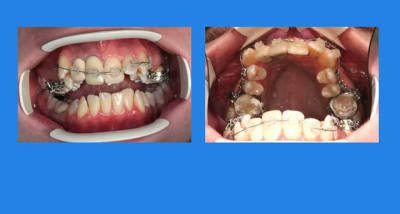

Début du cas :

pose mat Sup.

1 q4hjp9 - Eugenol

1 p3qrc4 - Eugenol